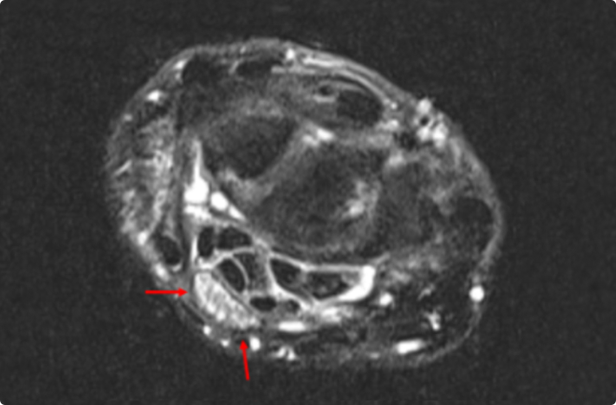

MRI 에서 다음과 같이 신경이 눌려 있고, 횡수근 인대 전단계에는 신경이 부어 있는 모습이 관찰되면

중증의 손목터널증후군으로 판단할 수 있습니다.